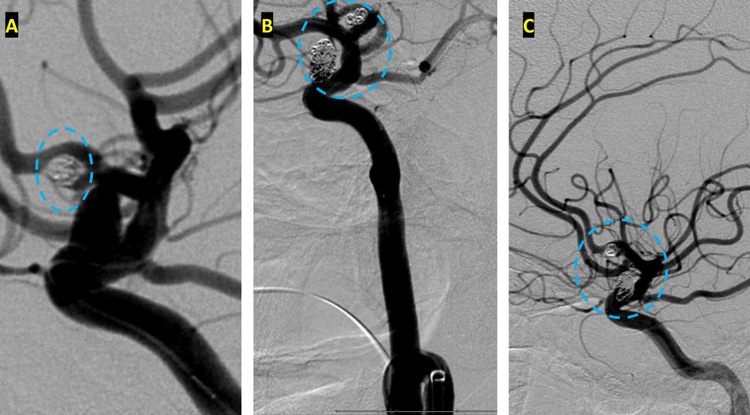

After careful measurements of the parent vessels, aneurysm sac, and aneurysm neck, we decided to proceed with Primary Coil Embolization of the Acom Aneurysm first, followed by the Right ICA Aneurysm next. Despite greater suspicion in the Acom region, a significant level of uncertainty remained, and we felt it was better to secure both aneurysms if capable of being performed safely. (Figure 4.)

After both aneurysms was secured, she spent 14 days in the Neurointensive Care Unit where she was monitored and treated for hydrocephalous and vasospasm. As a high-grade subarachnoid hemorrhage (WFNS Grade 4) patient, she underwent extensive critical care to manage cardiac, respiratory, DVT, seizure, and ID prophylaxis and treatment. During that period, she regained levels of consciousness, alertness, and neurologic function. Upon hospital discharge, she had regained all neurological functions, however remained globally weak and deconditioned. After 1 week in Acute Rehabilitation, receiving extensive physical and occupational therapy, she was able to return home, where she was independent and returning to all her activities of daily living at 1 month following her rupture event, mRS of 0.